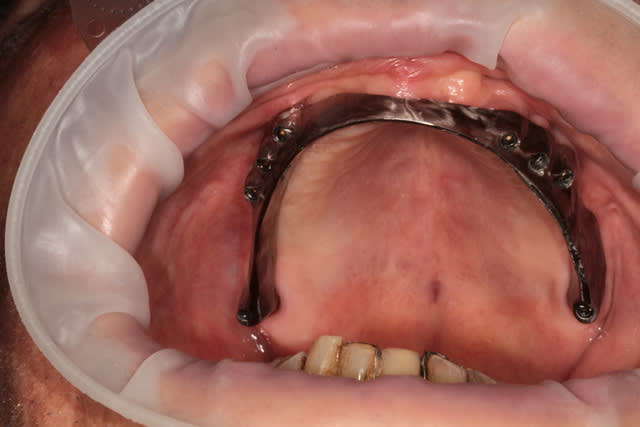

Bonsoir à tous je voudrais avoir votre avis sur ce cas :

8 implants maxillaires en vue d'une reconstitution fixe, je vous avoue que je pensais avoir pas trop mal placé au niveau axe (par rapport à certains de mes cas précédents ou la divergence était plus importante ) pourtant quand je veux verifier ma clef en platre pour valider mon empreinte, je ne parviens pas à insérer celle ci sans contraintes.

Sur le modèle en platre j ai le meme problème mais mon prothésiste me dit que çà vient de ma divergence d'axes implantaires

Ils sont vestibulés c'est sur mais cette orientation n'est elle pas naturelle du fait de la résorption maxillaire?

1. Le parallélisme entre les implants est pas mal du tout

2. Par contre il fallait redresser les axes en étant plus vers palatin que vestibulaire